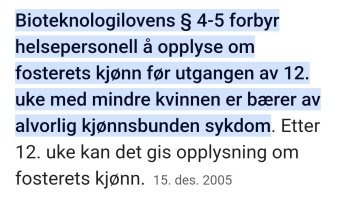

Det er ikke lov å oppgi dette i norge og i uke 12-13 er gutt og jente fortsatt så like at det blir mer et gjett. Guttene har heller ikke fått pung enda.Vet ikke hvor langt du er nå, men på de fleste kan man se kjønn på ultralyd rundt uke 12/13

Det er lov til å oppgi dette på UL jo. Eller hva mener du? Gutter og jenter har forskjellig nub fra uke 12 og de fleste jordmødre bruker «the nub theory» for å fastsette kjønn. Så det er mulig å se, men ikke 100% sikkert så klart fordi det er så tidlig.Det er ikke lov å oppgi dette i norge og i uke 12-13 er gutt og jente fortsatt så like at det blir mer et gjett. Guttene har heller ikke fått pung enda.

Fikk vite kjønn på toul i vår da vi var på UL daDet er ikke lov å oppgi dette i norge og i uke 12-13 er gutt og jente fortsatt så like at det blir mer et gjett. Guttene har heller ikke fått pung enda.

Det er lov til å oppgi dette på UL jo. Eller hva mener du? Gutter og jenter har forskjellig nub fra uke 12 og de fleste jordmødre bruker «the nub theory» for å fastsette kjønn. Så det er mulig å se, men ikke 100% sikkert så klart fordi det er så tidlig.

Utgangen av uke 12 (det er vel 11+6)?Ja, men det er lov etter uke 12. Jeg var 12+3

Vet ikke om det er 11+6 eller 12+0, men det er flere har som har fått vite 11+6 så sikkert det!Utgangen av uke 12 (det er vel 11+6)?